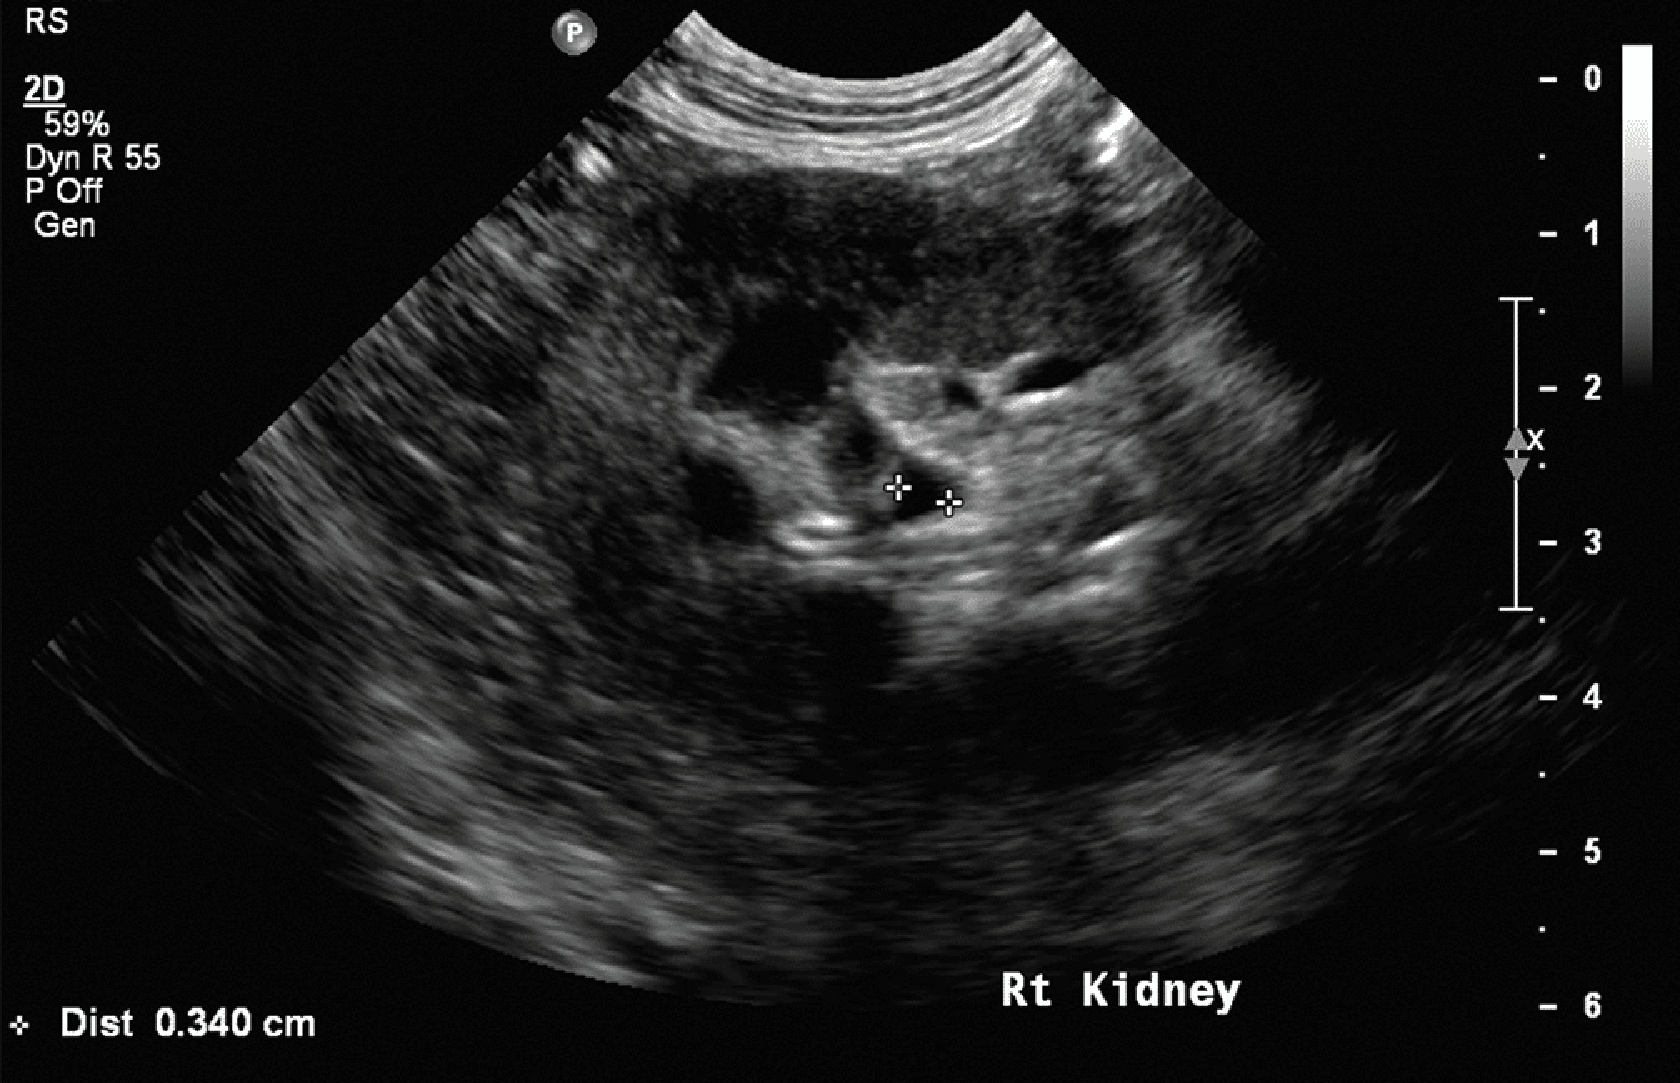

Zmniejszone zróżnicowanie korowo-rdzeniowe

Wyraźne zróżnicowanie między korą a rdzeniem nerki wynika z wyższej gęstości komórkowej w korze oraz większej zawartości płynów w rdzeniu nerki (ryc. 7).15 Wraz ze zwyrodnieniem i utratą zdolności zatrzymywania płynów w rdzeniu nerki echogeniczność rdzenia stopniowo wzrasta, co prowadzi do utraty zróżnicowania między korą a rdzeniem.15

Medium huguet ryc7 opt

Ryc. 7. Obraz w projekcji strzałkowej prawej nerki kota, ukazujący wyraźnie zmniejszone zróżnicowanie korowo-rdzeniowe, a także hiperechogeniczność kory nerki i jej nieregularne brzegi.